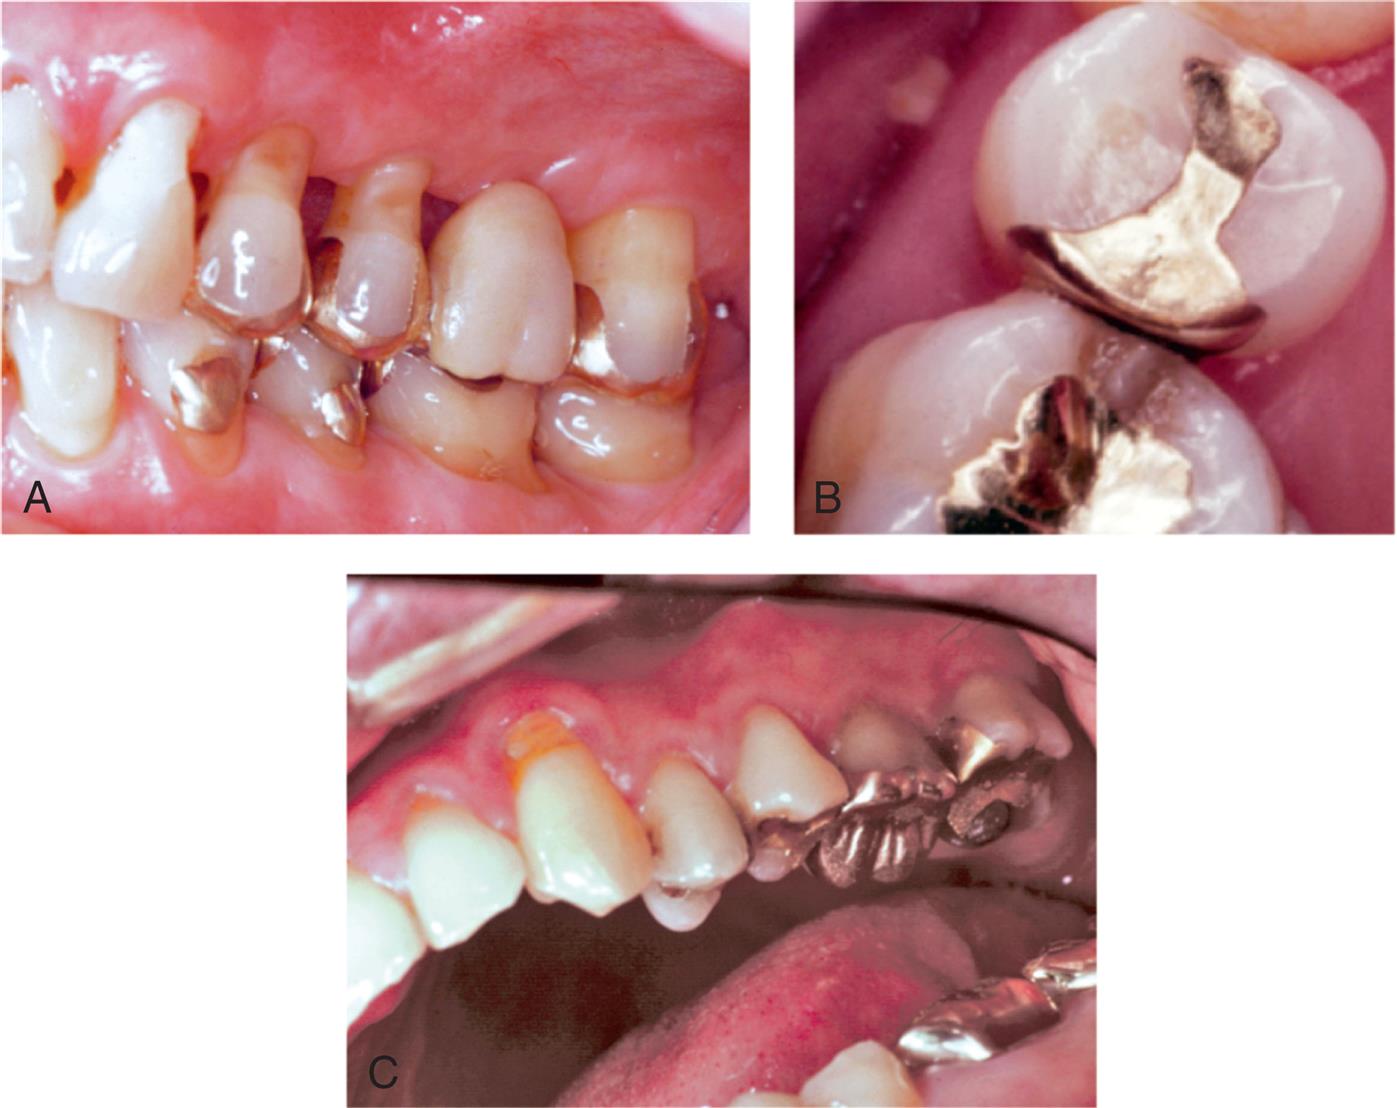

An extracoronal metal restoration that covers only part of the clinical crown is considered a partial veneer crown. It can also be referred to as a partial-coverage restoration. An intracoronal cast metal restoration is called an inlay, or an onlay if one or more cusps are restored. Examples of these restorations are presented in Fig. 11.1. Partial veneer crowns generally include all tooth surfaces except the buccal or labial wall in the preparation. Therefore these restorations preserve more of the tooth’s coronal tissue than does a complete crown. However, the preparation is more demanding and is not routinely provided by practitioners. Buccolingual displacement of the restoration is prevented by internal features (e.g., proximal boxes and grooves). Partial veneers can be used as single-tooth restorations or as retainers for a fixed partial denture (FPD). Although more often used on posterior teeth today, they can be used on both anterior and posterior teeth. Because they cover less of the coronal surface, partial coverage restorations tend to be less retentive than complete crowns and also less resistant to displacement. Inlays and onlays are even less retentive than partial veneer crowns. However, they provide the advantage of material strength (i.e., resistance to deformation) and preservation of tooth structure. Margins are generally more accessible, allowing improved finishing by the dentist, and cleaning by the patient. When carefully executed, inlays and onlays can be exceptionally long-lasting restorations (see Fig. 11.1).

Cast inlays and onlays can be extremely long-lived restorations because of the excellent mechanical properties of the gold alloy (see Fig. 11.1). Low creep and corrosion mean that if inlay or onlay margins are accurately cast and finished, they will not deteriorate. The lack of corrosion may also offer an esthetic advantage. Gold does not lead to the tooth discoloration sometimes associated with dental amalgam. Unlike an inlay or amalgam, an onlay can support cusps, reducing the risk of tooth fracture.

Fig. 11.29 shows some outstanding clinical examples of conservative cast inlays.

Clinical examples of onlay restorations are shown in Fig. 11.32.